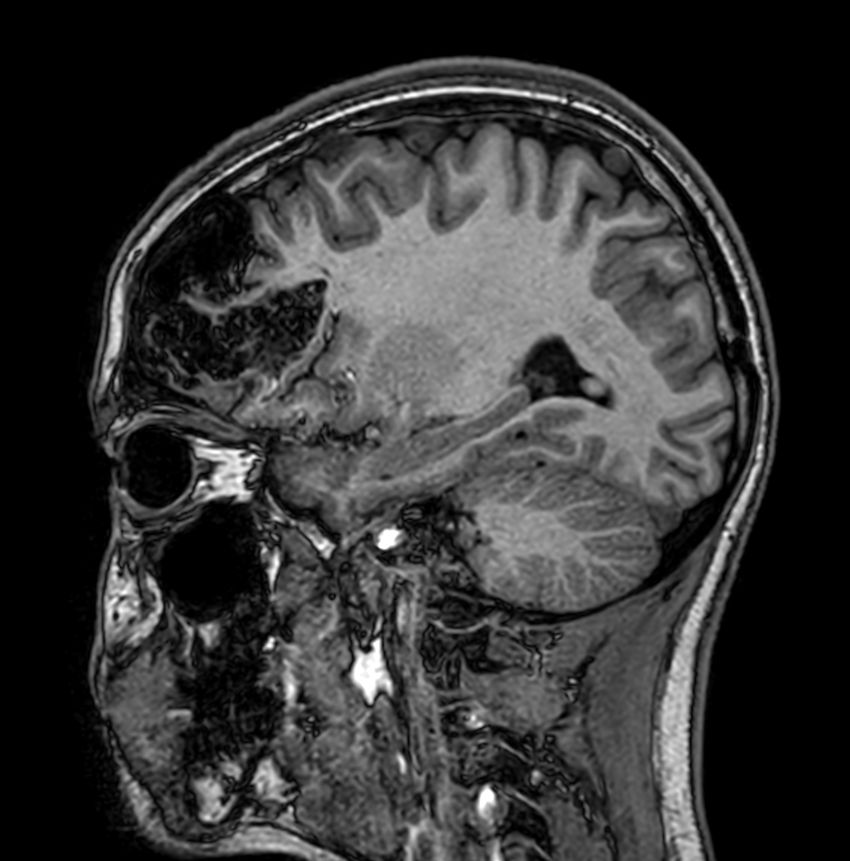

Sagittal 3D T1w TFECompressed SENSE

3D T1w TFE - Axial reformatCompressed SENSE